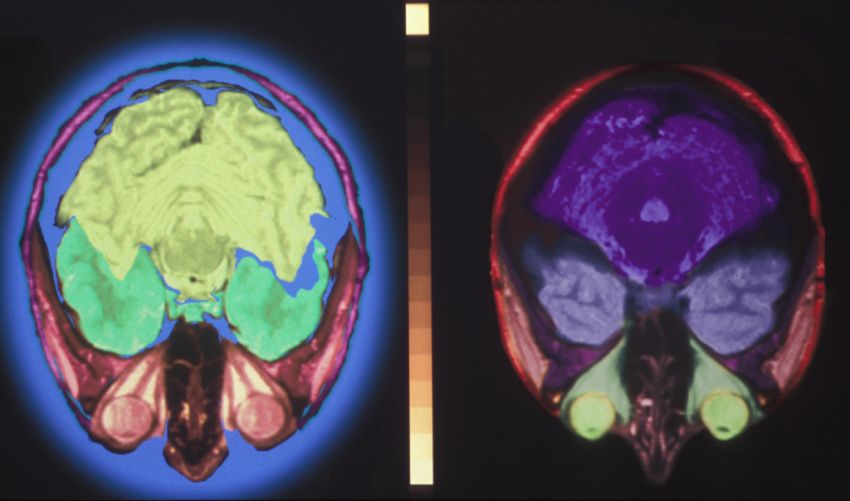

AccueilDossiersComaComa La plus sévère d’altération de la conscience Publié le : 15/10/2013 Temps de lecture : 6 minLe coma correspond à la forme la plus sévère d’altération de la conscience. Un patient dans le coma semble endormi, mais il ne réagit à aucune stimulation, même douloureuse. Cet état, généralement transitoire, peut s’observer dans un grand nombre de maladies, neurologiques ou non.Dossier réalisé en collaboration avec Benjamin Rohaut, unité de réanimation neurologique, pôle des maladies du système nerveux et Institut du cerveau et de la moelle épinière (ICM), unité Inserm 975, Neuropsychologie et neuroimagerie, GH-Pitié-Salpêtrière, ParisComprendre le comaDu coma à l’état végétatifLe coma est la forme la plus sévère d’altération de la conscience. Il s’agit en général d’un état transitoire, durant au maximum quelques semaines. Dans les cas les plus graves son évolution peut conduire au décès. Dans les cas les plus favorables, le retour à la conscience est rapide, se produisant au bout de quelques jours. Mais le plus souvent, l’amélioration est lente et peut passer par d’autres états de conscience altérée, tels que l’état végétatif et l’état de conscience minimale. L’état végétatif est défini par une ouverture spontanée des yeux, mais sans conscience. Certains mouvements réflexes sont possibles, notamment des mouvements des yeux, mais sans poursuite visuelle. L’état de conscience minimale (ou état pauci-relationel) est défini par une ouverture des yeux avec une conscience « partielle » possible, mais insuffisante pour qu’une communication fonctionnelle puisse s’établir. On observe souvent certains gestes non réflexes, notamment une poursuite visuelle. Cerveau humain en IRM, coupe sagittale © InsermLe coma n’est pas la mort cérébrale La mort cérébrale est définie par l’absence totale et définitive de l’activité cérébrale. Le contrôle des fonctions dites végétatives (respiration, contrôle du système cardiovasculaire…) n’est plus assuré. Le cœur du patient bat encore (temporairement) grâce aux techniques d’assistance de réanimation. C’est dans cette situation que se pose la question du don d’organe envers un tiers.Des causes nombreuses et variéesLe coma peut être la conséquence d’une altération directe du système de l’éveil, situé dans une structure profonde du cerveau (le tronc cérébral), d’où les neurones se projettent largement vers le reste du cerveau et régulent le cycle veille-sommeil. Il peut aussi être la conséquence d’un processus plus diffus, affectant l’ensemble du cerveau (cortex et/ou substance blanche).Les causes les plus fréquemment responsables d’un coma sont : les traumatismes crâniensl’hypoxie/ischémie cérébrale,les accidents vasculaires cérébraux (hémorragiques surtout)les surdosages médicamenteux/toxiquesles états de mal épileptiquesles encéphalites, méningo-encéphalites et abcès cérébrauxles encéphalopathies (métaboliques, dysimmunes…)les tumeurs cérébralesLe pronostic d’un coma dépend beaucoup de sa cause. Certaines d’entre elles – comme les causes métabolique/toxique, les états de mal épileptiques ou les encéphalopathies – sont généralement de meilleur pronostic que les causes vasculaires ou hypoxiques qui entrainent l’absence d’oxygénation temporaire d’une région plus ou moins étendue du cerveau. Tenter d’identifier la cause dès la prise en chargeLes premières étapes de la prise en charge d’un patient dans le coma consistent à évaluer rapidement ses fonctions vitales (voies respiratoires dégagées, bonne oxygénation du sang, niveau de pression artérielle correcte) et, si besoin, à mettre rapidement en place les mesures de réanimation nécessaires (support ventilatoire, hémodynamique…). Son degré d’altération de la conscience est évalué à l’aide d’un score (de Glasgow), cotant les réponses verbale, oculaire et motrice à différentes stimulations physiques. Un patient dans le coma est en général admis dans un service de réanimation médicale ou chirurgicale. Il s’agit ensuite d’identifier la cause du coma. Certains examens ou tests pharmacologiques permettent d’éliminer des causes rapidement réversibles (hypoglycémie, surdosage en morphinique ou en benzodiazépine). Une imagerie cérébrale (scanner ou IRM) est souvent pratiquée, pour éliminer une pathologie nécessitant un geste chirurgical urgent. Le recueil détaillé des antécédents et des circonstances de survenue du coma, associé à l’examen neurologique permettent le plus souvent d’orienter les médecins vers la cause du coma. Des examens complémentaires sont ensuite souvent nécessaires pour confirmer le diagnostic (imagerie cérébrale, ponction lombaire, électroencéphalogramme et bilan biologique). Le devenir des patients, souvent difficile à prévoirPrévoir le devenir du patient est un enjeu majeur, notamment lorsque le coma se prolonge ou que le patient reste dans un état de conscience altéré (état végétatif ou de conscience minimale). La poursuite de la réanimation n’a en effet plus de sens si l’on arrive à la certitude qu’il n’y a plus d’espoir de récupération. Dans certaines situations, l’évaluation du pronostic est relativement simple. Ainsi, dans les comas post-anoxiques (causé par une interruption dans l’oxygénation du cerveau), de nombreuses études ont permis de définir des critères pronostics très fiables. L’abolition de réflexe pupillaire ou cornéen ou un score moteur de Glasgow inférieur à 2 au troisième jour de la prise en charge sont des facteurs de très mauvais pronostic. Dans d’autres situations l’évaluation est plus délicate et fait appel, en plus du suivi de l’examen clinique qui est fondamental, à des explorations complémentaires : - des explorations électrophysiologiques, électroencéphalographie et potentiels évoqués (enregistrement de l’activité électrique du système nerveux), qui permettent d’explorer le degré de fonctionnement cérébral résiduel - des examens d’imagerie cérébrale (scanner, IRM), qui permettent de quantifier l’étendue des lésions cérébrales éventuelles. En l’absence d’amélioration, un état végétatif est dit « persistant » après un mois. On parle d’état végétatif permanent après 3 mois en cas de lésion cérébrale non traumatique, et après 12 mois en cas de lésion cérébrale traumatique. De nombreuses études se fondant sur le suivi de patients ont montré que la probabilité de récupération devient alors quasi nulle.Scanner du cerveau © Inserm / Alpha PictCommuniquer avec une personne dans le coma ?Par définition, un patient dans le coma n’est pas conscient. On ne peut donc pas communiquer avec lui. Mais le diagnostic reposant sur l’évaluation des réponses du patient, il peut exister des situations (très rares) où un patient diagnostiqué à tort comateux est en réalité conscient. L’exemple classique est celui du « locked-in syndrome » dans lequel le patient est presque entièrement paralysé. Si après un examen neurologique approfondi un doute subsiste sur le niveau de conscience d’un patient, certaines techniques d’imageries fonctionnelles peuvent parfois conduire à la mise en évidence d’une telle situation. Ces cas sont toutefois extrêmement rares. REVE, la recherche de la conscience – reportage et interview – 6 min – film extrait de la série Des idées plein la tech’ (2013) Les enjeux de la recherchePour préciser le pronostic des patients récupérant lentement, plusieurs équipes de recherche tentent actuellement d’identifier des marqueurs pronostiques plus performants, notamment à l’aide d’explorations fonctionnelles sondant les capacités résiduelles du fonctionnement cérébral, ou de techniques d’imageries plus sensibles, permettant de détecter des lésions cérébrales qui peuvent passer inaperçues avec les techniques couramment utilisées. Nos contenus sur le même sujetActualités11/10/21 La réponse cardiaque à l’écoute d’un récit serait prédictive de l’état de conscience16/02/15 Repos conscient ou inconscient : des signatures d’activités cérébrales distinctes16/10/13 Un nouvel outil pour évaluer l’état de conscience des patients sortant du comaCommuniqués de presse30/05/24 Un meilleur pronostic de retour à la conscience des patients placés en réanimation21/03/22 Restaurer la conscience grâce à une stimulation profonde du cerveau25/06/20 Troubles de la conscience : deux nouvelles découvertes fondamentales pour le diagnostic et le traitement des patients25/02/19 L’expertise des soignants contribue à améliorer le diagnostic des patients en état de conscience altérée23/10/17 Interaction entre cœur et cerveau : un nouvel indicateur de l’état de conscience11/11/15 Un indicateur pour prédire la sortie du comaPour aller plus loin Coma et états végétatifs – émission La tête au carré (France Inter) du 20 janvier 2015 avec Steven Laureys Le Coma – La tête au carré (France Inter), émission du 12 février 2013. Avec Louis Puybasset, Damien Galanaud et Lionel Naccache – émission La tête au carré (France Inter) du 12 février 2013, avec Louis Puybasset, Damien Galanaud et Lionel Naccache Grâce à l’IRM, on peut prédire si un malade va sortir du coma – reportage diffusé sur France 2 le 25 février 2013 Coma : cas de conscience – reportage de l’émission 36,9° diffusé par le RTSR le 8 février 2012